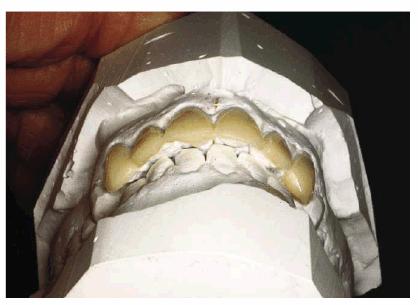

Figure 24-4D: Diagnostic cast-facial view.

Figure 24-4E: Diagnostic cast-incisal view. By measuring the available arch space for each incisor, the source of the crowding problem was determined. The results of this analysis demonstrated a 1.5-mm deficiency in the area of tooth #7 and an excessive amount of arch space with tooth #8.